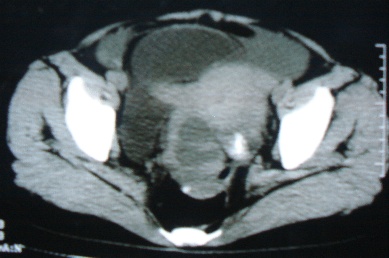

标题: CT8388:女,48岁。感腹胀一周,请会诊

ct10755,女,48岁。感腹胀一周入院。

考虑右侧卵巢囊腺癌并腹腔转移、子宫肌瘤

支持右侧卵巢囊腺癌并腹腔转移

考虑右侧卵巢囊腺癌并腹腔转移可能性大、子宫肌瘤

支持:右侧卵巢囊腺癌并腹腔转移,或囊腺瘤破裂腹腔种植。

支持:右侧卵巢囊腺癌并腹腔转移、腹水、盆腔积液。

卵巢囊腺癌并腹腔转移、腹水、盆腔积液。

考虑为右侧卵巢囊腺癌并腹腔转移、腹水、盆腔积液.

右侧卵巢囊腺癌并腹腔转移,腹水。

支持右侧卵巢囊腺癌并腹腔转移(大量腹水)。